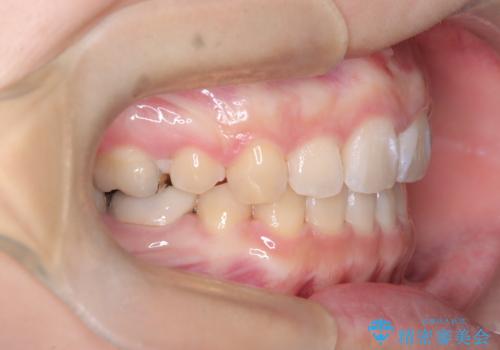

- 口元が出ている(突出している)ことを気にされて来院されました。精密な検査の結果、前歯を大きく後退させるスペースが必要と診断。患者様の**「前歯を下げたい」という強いご要望に応えるため、上下左右の第一小臼歯を抜歯し、そのスペースを利用して前歯を奥へ移動させる治療計画を立案しました。また、人目を気にせず治療できるよう、上顎に裏側矯正、下顎に表側矯正を組み合わせたハーフリンガル矯正**を提案しました。

今回の矯正治療では、前歯を大きく後退させるスペースを確保するため、計画通り上下左右の第一小臼歯を抜歯しました。装置には、上顎には目立たない裏側矯正(舌側矯正)を、下顎には透明な審美ブラケットを使用するハーフリンガル矯正を採用しました。抜歯によってできたスペースを最大限に活用し、前歯を効率よく後方へ移動。治療の結果、口元の突出感が大幅に解消され、Eライン(横顔の美しさの基準)も改善しました。人目を気にすることなく治療を完遂し、自信の持てる美しい横顔を獲得していただけました。